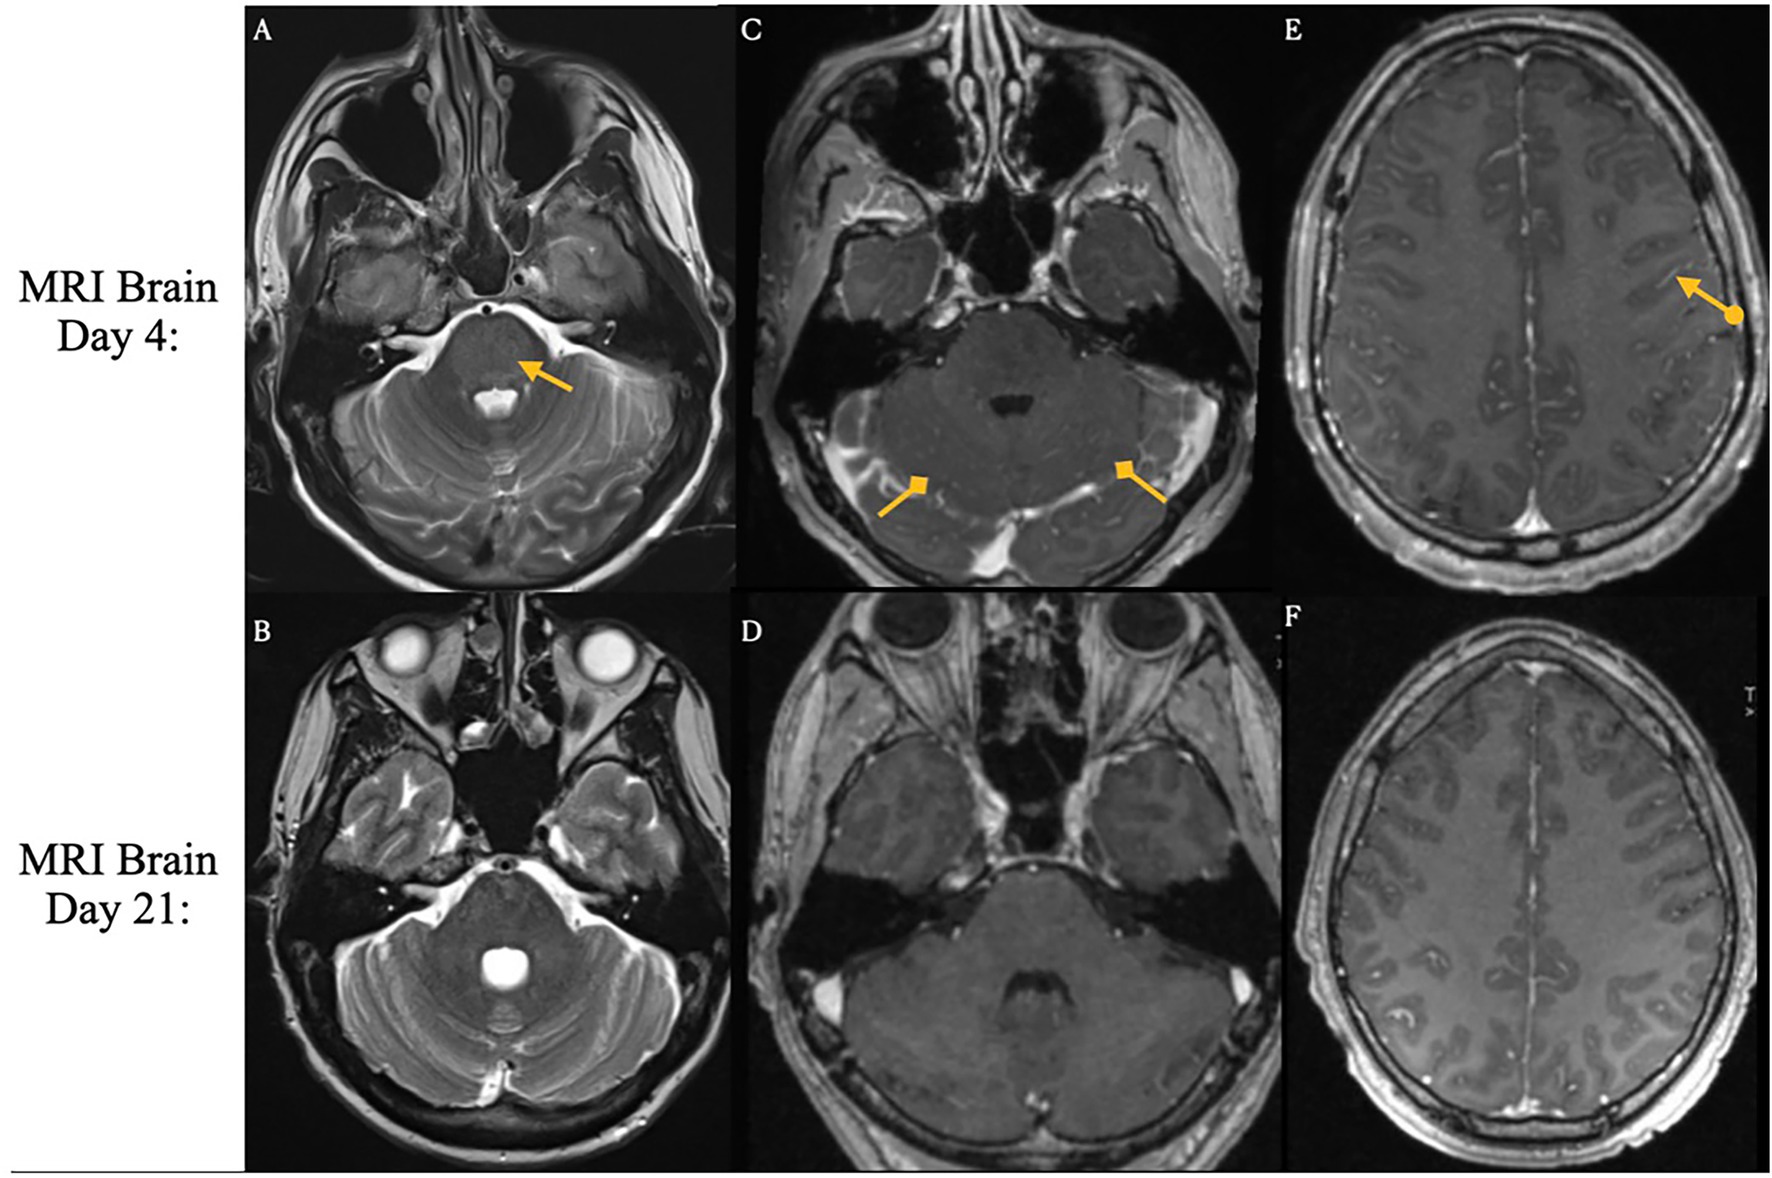

On day nine following Yescarta infusion, the patient was extubated and noted to have new-onset bilateral lower extremity paresis, areflexia, and sensory loss up to the level of the umbilicus. MRI revealed diffuse T2 hyperintensity throughout the cervical cord, thoracic cord, and conus medullaris (Figure 5). He was empirically initiated on intravenous immunoglobulin (IVIG, 0.4 g/kg for 5 days) while continuing dexamethasone and anakinra therapy. Although neuroimaging showed improvement with this regimen, the patient’s lower extremity weakness persisted without clinical recovery. By day 21, repeat MRI demonstrated complete resolution of the initial brain and spine abnormalities; however, new findings emerged in the conus medullaris, including clumping of the ventral nerve roots (Figure 6). Cerebrospinal fluid (CSF) analysis revealed elevated protein (101 mg/dL), leukocytosis (23 cells/μL), normal glucose (61 mg/dL), and no evidence of malignancy. Infectious cultures, ganglioside antibodies, aquaporin-4, paraneoplastic antibodies, and oligoclonal bands were all negative in the CSF.

Figure 6

Three MRI images labeled A, B, and C show different views of a spinal area. Images A and B feature yellow arrows indicating specific points of interest within the spinal structure, possibly highlighting areas of abnormality or concern. Image C lacks an arrow but continues the sequence for contextual comparison.

Figure 6. Spinal magnetic resonance imaging on day 21 post-treatment. New clumping and enhancement of the ventral cauda equina nerve roots observed on day 21 after treatment for ICANS and prophylactic IVIG (Panels A,B,C).

Both the present case and the case described by Koch et al. developed immune effector cell associated neurotoxicity syndrome. In the Koch et al. case, the patient exhibited simultaneous onset of grade 2 ICANS (disorientation) and GBS-like symptoms on day five, with no ICANS related findings on brain MRI. In contrast, our patient developed grade 1 ICANS on day three, which progressed to grade 3 (aphasia) and grade 4 (seizures) by day four. Brain MRI in our presented case revealed imaging features typical of ICANS, including leptomeningeal enhancement and diffuse T2/FLAIR hyperintensities in the cortex and pons. These findings resolved with treatment using dexamethasone and anakinra. However, following extubation on day nine, the patient developed new-onset neurological deficits and spinal MRI findings consistent with Guillain-Barré syndrome following apparent resolution of ICANS.

Among the six cases with both peripheral and cranial neuropathies, four (reported by Rutenburg et al., Raju et al., and Miller et al.) showed initial cranial nerve deficits followed by delayed onset of peripheral neuropathies, with delays ranging from 2 weeks to 2 months in cases with available data (31, 34, 36, 37). In four of these six cases, MRI findings were limited to abnormal gadolinium enhancement of the facial nerve, despite concurrent peripheral involvement (3133, 36) In the remaining two cases, Koch et al. and Miller et al. (Patient 4) described similar facial nerve enhancement, with additional clumping and thickening of the cauda equina roots. In contrast, our patient, who presented with only peripheral symptoms, demonstrated distinct conus medullaris abnormalities with ventral nerve root clumping on spine MRI (Table 1).

Four of the described patients also presented with peripheral nerve findings on spinal MRI. Similar to typical GBS, these findings included abnormal nerve root enhancement and nerve root thickening. Two cases involved the cauda equina, one affected the conus medullaris, and the last showed diffuse enhancement throughout the cervical, thoracic, and lumbar spine. While GBS usually affects the lumbosacral region, enhancement can extend throughout the cauda equina and conus medullaris (71, 72).

Albuminocytologic dissociation, defined as an increased protein level (>0.45 g/L) in the absence of elevated white cell count (<50 cells/μL) was seen in 90% of cases (Table 2). While most reports of typical GBS have cell counts <5, many cases here also had a mild lymphocytic pleocytosis, reflecting an inflammatory response within the central nervous system (73, 74). Intravenous immunoglobulin is currently the standard of care for GBS to enhance recovery and reduce disability by modulating the causative autoimmune pathophysiology. IVIG acts to neutralize harmful autoantibodies including anti-ganglioside antibodies, block Fc receptors, inhibit complement activation, and downregulate inflammatory cytokines (7577). Finally, while IVIG was administered in nearly all reported cases, many patients—including our own—did not demonstrate clear or immediate clinical improvement. In fact, our described patient went on to develop progressive imaging anomalies even after prophylactic IVIG was given (Figure 6), highlighting the uncertainty of IVIG efficacy in this context. If the pathogenesis is not primarily antibody-mediated, the standard therapeutic effect of IVIG may be reduced in this setting, leading to incomplete neurological recovery. These findings underscore the need for further research into the mechanisms underlying CAR-T–associated GBS and the development of targeted treatment strategies beyond conventional GBS management to prevent.